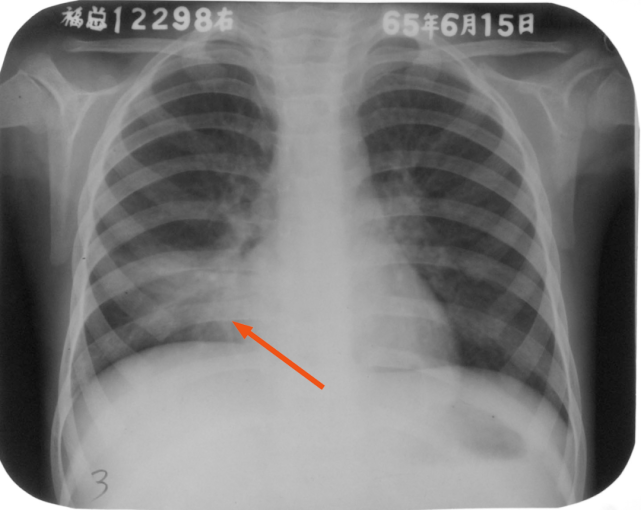

右肺中叶大叶性炎症

图片

胸部正位片:右肺中叶见片状致密影,边缘模糊(箭头所示)